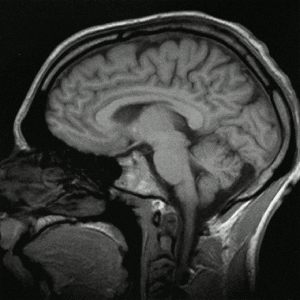

Herófilo de Calcedonia fue otro de los grandes médicos de esta escuela: describió con acierto las estructuras denominadas meninges, los plexos coroideos y el cuarto ventrículo cerebral.